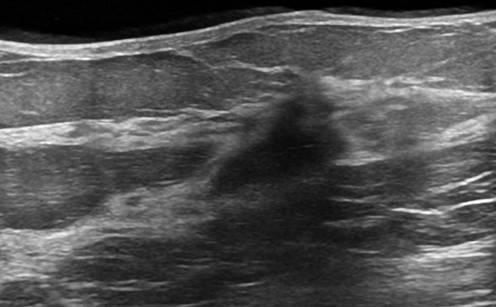

Ung thư vú

Ung thư vú - Ảnh 3

Ung thư vú - Ảnh 4

» Thông tin: Nữ giới – 50 tuổi.

» Lâm sàng: Khối tuyến vú.